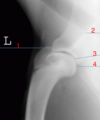

Name the view seen here

Lateromedial

Identify Structure #1

tibia

Identify Structure #2

calcaneous

Identify Structure #3

chestnut

Identify Structure #4

tarsocrural joint

Identify Structure #5

proximal intertarsal joint

Identify Structure #6

Distal intertarsal joint

Identify Structure #7

tarsometatarsal joint

Identify Structure #8

metatarsal 3